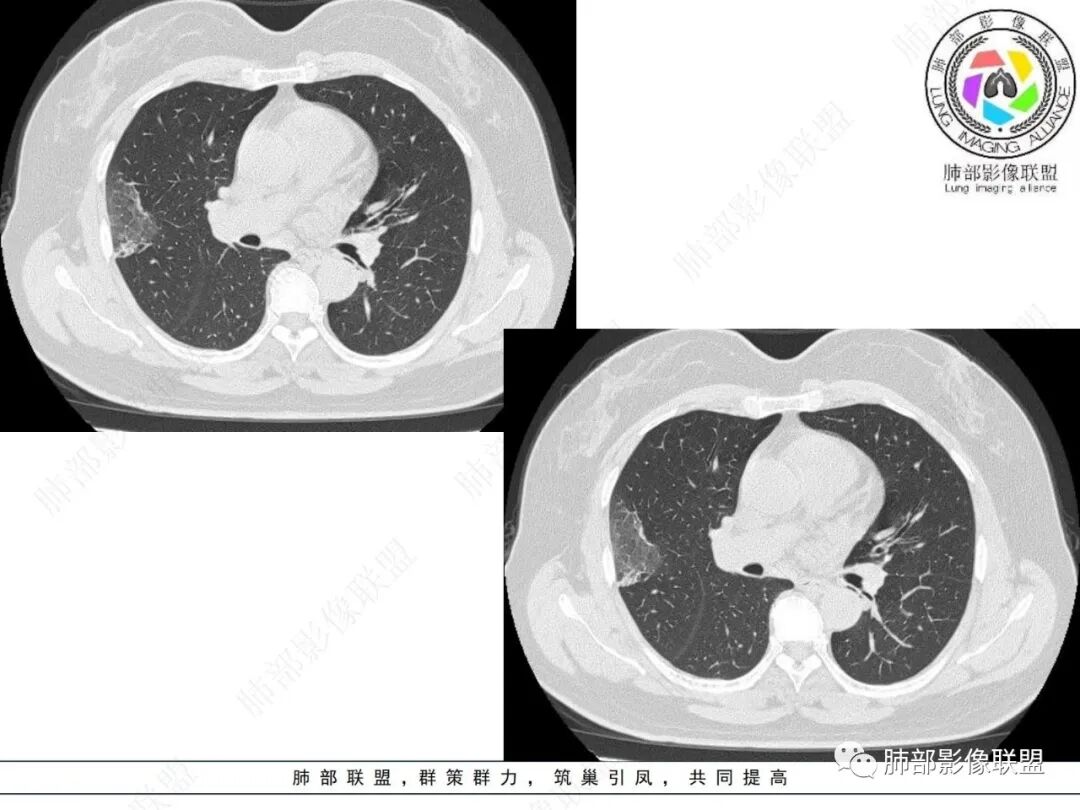

2.影像特点:

右肺上叶胸膜下混合磨玻璃团片影。

周围磨玻璃部分间杂条索状高密度区,密度欠均匀(可疑重力分布趋势),其磨玻璃影边界大多较清楚或可分辨,部分“L型”边缘,提示小叶间隔阻挡可能。血管穿行自如,可疑远端支气管进入。

实性部分较密实,不规则,隐约见棘突或刺状突起,未见钙化、空洞或液化区,实性边缘可见斑状略低密度间隙(借用王兆宇老师课件,称其呈“松软”的形态)。动脉期实性部分较明显不均匀强化,如果有完整增强图,还可以观察内部血管情况。

纵隔窗相对肺窗病灶相对小,仅部分实性影呈现。病灶张力不高,相邻胸膜增厚(糊墙),未见明显胸膜牵拉凹陷。

未见卫星病灶,远处未见磨玻璃结节影。

双肺门及纵隔未见明显增大淋巴结。心包及胸腔未见积液。